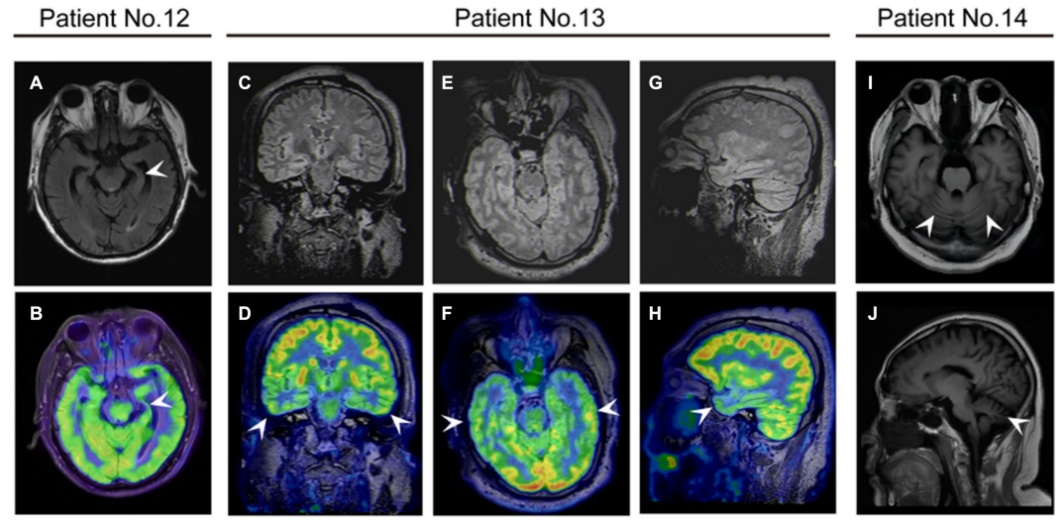

42.9%µÄ»¼ÕßÓÐMRIÒì³££¬°üÀ¨Æ¤ÖÊÔöÇ¿¡¢°×Öʸı䡢º£ÂíÖ×ÕÍ»òήËõÒÔ¼°Ð¡ÄÔήËõ¡£2Àý»¼Õß18F-FDG PET/MRIÌåÏÖΪò¨Ò¶¼°ÇðÄԵʹúл£¬Ó뻼ÕßÁÙ´²Ö¢×´Ò»Ö¡£¿¹DPPX¿¹ÌåÄÔÑ×»¼ÕßMRI¶àÎÞÌØÒìÐÔ [5]£¬18F¡ªFDG PET¶ÔÃ÷È·¿¹DPPX¿¹ÌåÄÔÑ×ÂÄÚ´úлģʽ¡¢Ìá¸ßÑôÐÔ¼ì³öÂÊ¿ÉÄÜÓÐËù×ÊÖú[2]¡£

¿¹DPPXÄÔÑ×»¼ÕßµÄÉñ¾Ó°ÏñѧÌåÏÖ¡£(A£¬B)12ÀýÈÏÖªÕϰ»¼ÕߴʲÕñ³ÉÏñ(MRI)ÏÔʾ×ó²àº£ÂíήËõ£¬Õýµç×Ó·¢Éä¶Ï²ãɨÃèÏÔʾ×ó²àº£Âí18F-·úÍÑÑõÆÏÌÑÌÇ(FDG)ÉãÈ¡ïÔÌ(Õýµç×Ó·¢Éä¶Ï²ãɨÃè)/ºË´Å¹²Õñ³ÉÏñ¡£13ÀýÈÏÖª¹¦Ð§Õϰ»¼ÕßÔÚPET/MRI¹Ú״λ(E£¬F)ÖáλºÍʸ״λ(G£¬H)ÏÔʾ˫²àò¨Ò¶1¡ãF-FDGÉãÈ¡ïÔÌ¡£(1,J)¹²¼Ãʧµ÷»¼Õß14ÀýMRIÏÔʾСÄÔήËõ¡£